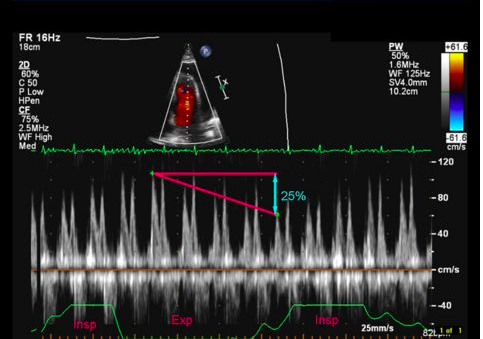

While not a necessary component of the EMBU to diagnose tamponade physiology, you can also use pulsed-wave Doppler to visualize pulsus paradoxus. In the apical 4-chamber view, obtain tracings of either the mitral valve or tricuspid valve. There is normally not much variation in the velocity of blood flow across the valve in diastole. In tamponade, regular flow variations with respirations are exaggerated since the cardiac chambers are smaller and unable to fully expand. Variation of maximum velocity flow across the valve >25% during inspiration is consistent with tamponade:

(image from http://web.stanford.edu/group/ccm_echocardio/cgi-bin/mediawiki/index.php/Tamponade)